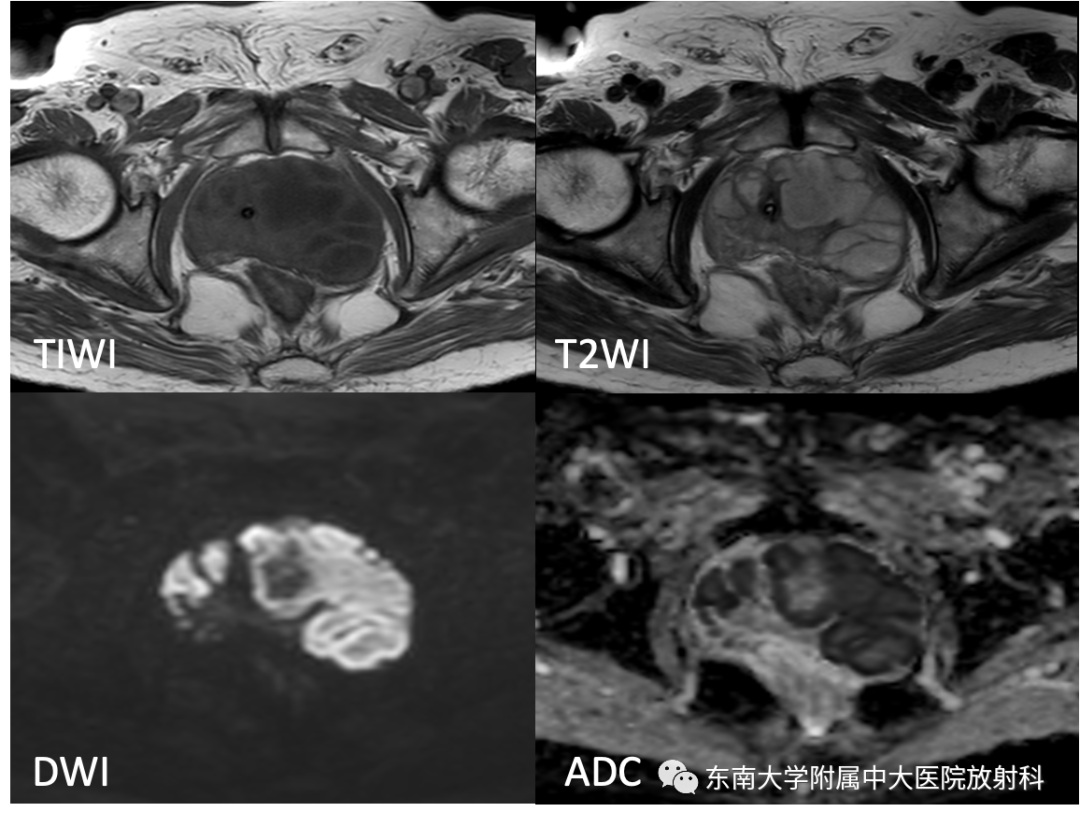

病史

男,68岁,发烧伴肛周疼痛1月

既往史:10月前于外院行“直肠癌根治术”,病理为中分化腺癌

B超提示:前列腺左侧叶低回声团,占位?